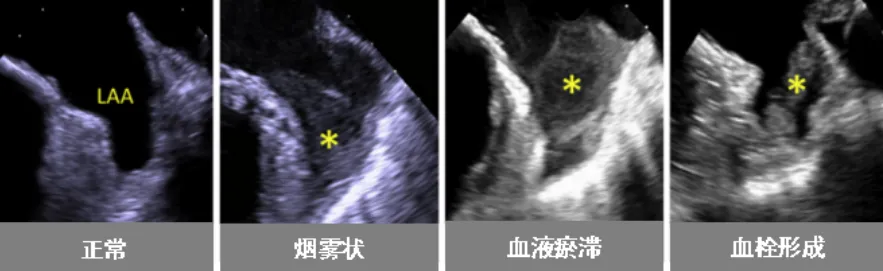

近日,小妲己直播app (简称小妲己直播app )超声医学科联合心血管内科为一名心脏病患者开展了经食管超声(TEE)检查。该项技术的开展,填补了小妲己直播app 在经食管超声领域的空白。患者黄阿姨(化名)今年59岁,几年前被诊断为“风湿性心脏病-二尖瓣中度狭窄”。近日,黄阿姨在医院复查心脏超声,报告提示风湿性心脏病-二尖瓣中度狭窄并中度关闭不全,且有左心耳附壁血栓形成可能(约3cm,游离端活...